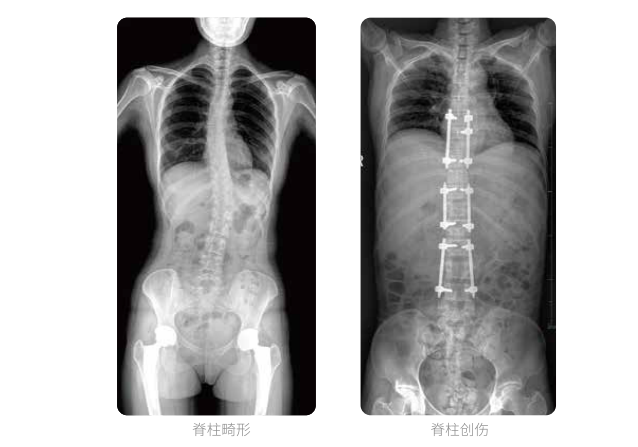

大視野不拼接 一次曝光覆蓋全脊柱

全脊柱臨床影像

PLX8600大視野平板動態DR全脊柱一次成像攝片適用于兒童、成人、老年人腰椎退行性病變、強直性脊柱炎、脊柱結核等臨床應用,在此類大視野的臨床拍攝中發揮了極大的價值。

PLX8600大視野平板動態DR可在透視情況下多角度觀察病灶部位,做術前診斷及術后愈合的檢查,如脊柱斜位透視,可觀察椎弓根峽部,診斷椎體是否滑脫等情況;可在脊柱運動狀態下通過透視模式觀察全脊柱狀態,了解病變處脊柱的活動度及骨結構的關系,配合點片功能快速獲得高清的關鍵幀影像,輔助醫生制定更準確的手術方案。